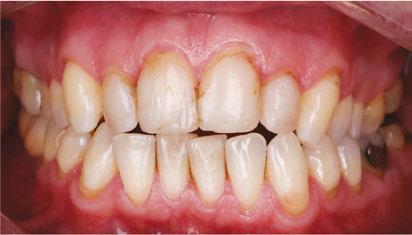

Drs. Claudia Pinter and Stanley Liu illustrate a protocol to improve nasal breathing in orthodontic care 31